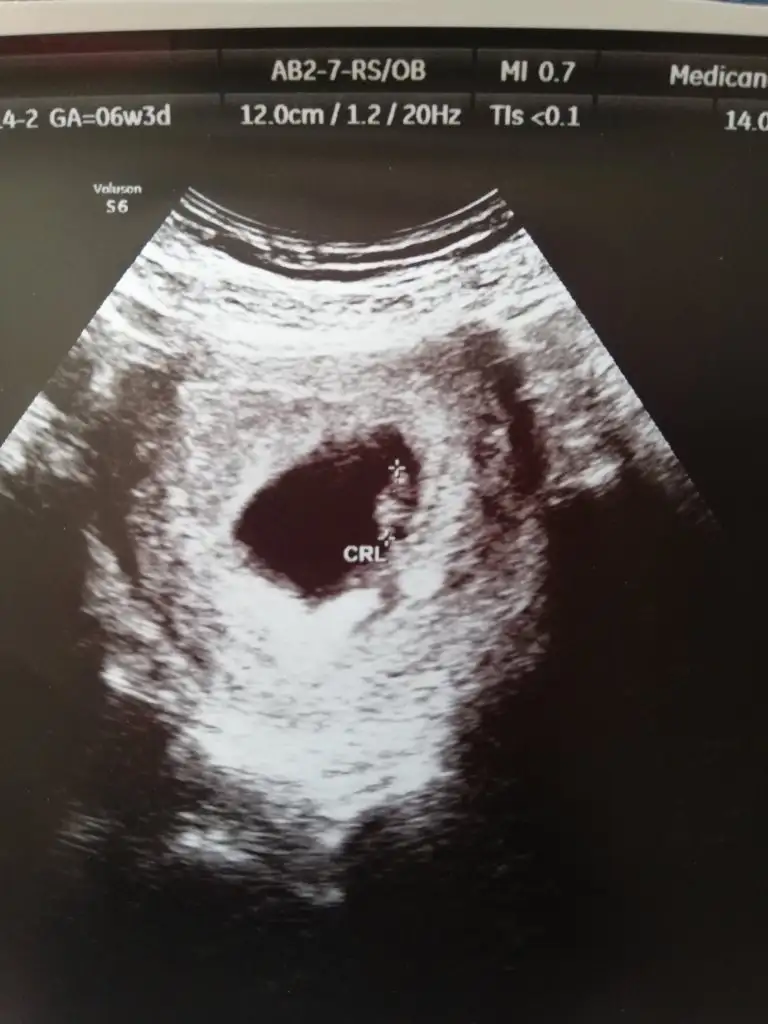

Bu ikinci gebeliğim, ilkinde bir damla bile kanama olmamıştı, hatta onda gebeliği öğrendikten 20 gün sonra ilk doktor kontrolüne gitmiştim rahatlığa bak

Ama bu farklı oldu, çok yorgun yoğun ve stresli bir döneme denk geldi, haftaya taşınıyoruz ve ben iki haftadır evde eşya topluyorum, haliyle yorucu geçiyor.

Açıkçası bu dönem beni endişelendiren tek konu kızımı kucağımda taşımak, taşınma aşamasındaki işler vs bu kanama durumlarını nasıl etkiler, eşim işten gelene kadar çocukla tek başıma ilgileniyorum ve taşınma sırasında yardıma gelebilecek kimse de yok

Canım bende de var kasık bel ağrısı arada artıyor azalıyor doktor normal dedi. Kanama oluyor zaten hemen arkasına düşük olursa bnm bi düşüğüm var onda çok şiddetli ağrım başladı birden kanamayla progestanda kullanıodum. Çok mu şiddetli ağrıların kanama lekenlenmen var mı varsa ne zamandır varGünaydın kızlar.progestan kullanıyorum günde 3 kere ama bel ağrılarım devam ediyor.biliyorsunuz sağlıklı bir düşük yapmayı da geciktiriyor bu takviye.sorum şu ki daha önce progestan ile düşük riskini atlatan varsa içinizde,bu bel ağrılarının kesilmesine etki etmemesini yaşayan var mı? Biliyprsunuz doktorlar kasık ve bel ağrısında dayıyor bunu hemen...bir nebze etkisi olur dedim ama

Günaydın kızlar.progestan kullanıyorum günde 3 kere ama bel ağrılarım devam ediyor.biliyorsunuz sağlıklı bir düşük yapmayı da geciktiriyor bu takviye.sorum şu ki daha önce progestan ile düşük riskini atlatan varsa içinizde,bu bel ağrılarının kesilmesine etki etmemesini yaşayan var mı? Biliyprsunuz doktorlar kasık ve bel ağrısında dayıyor bunu hemen...bir nebze etkisi olur dedim ama